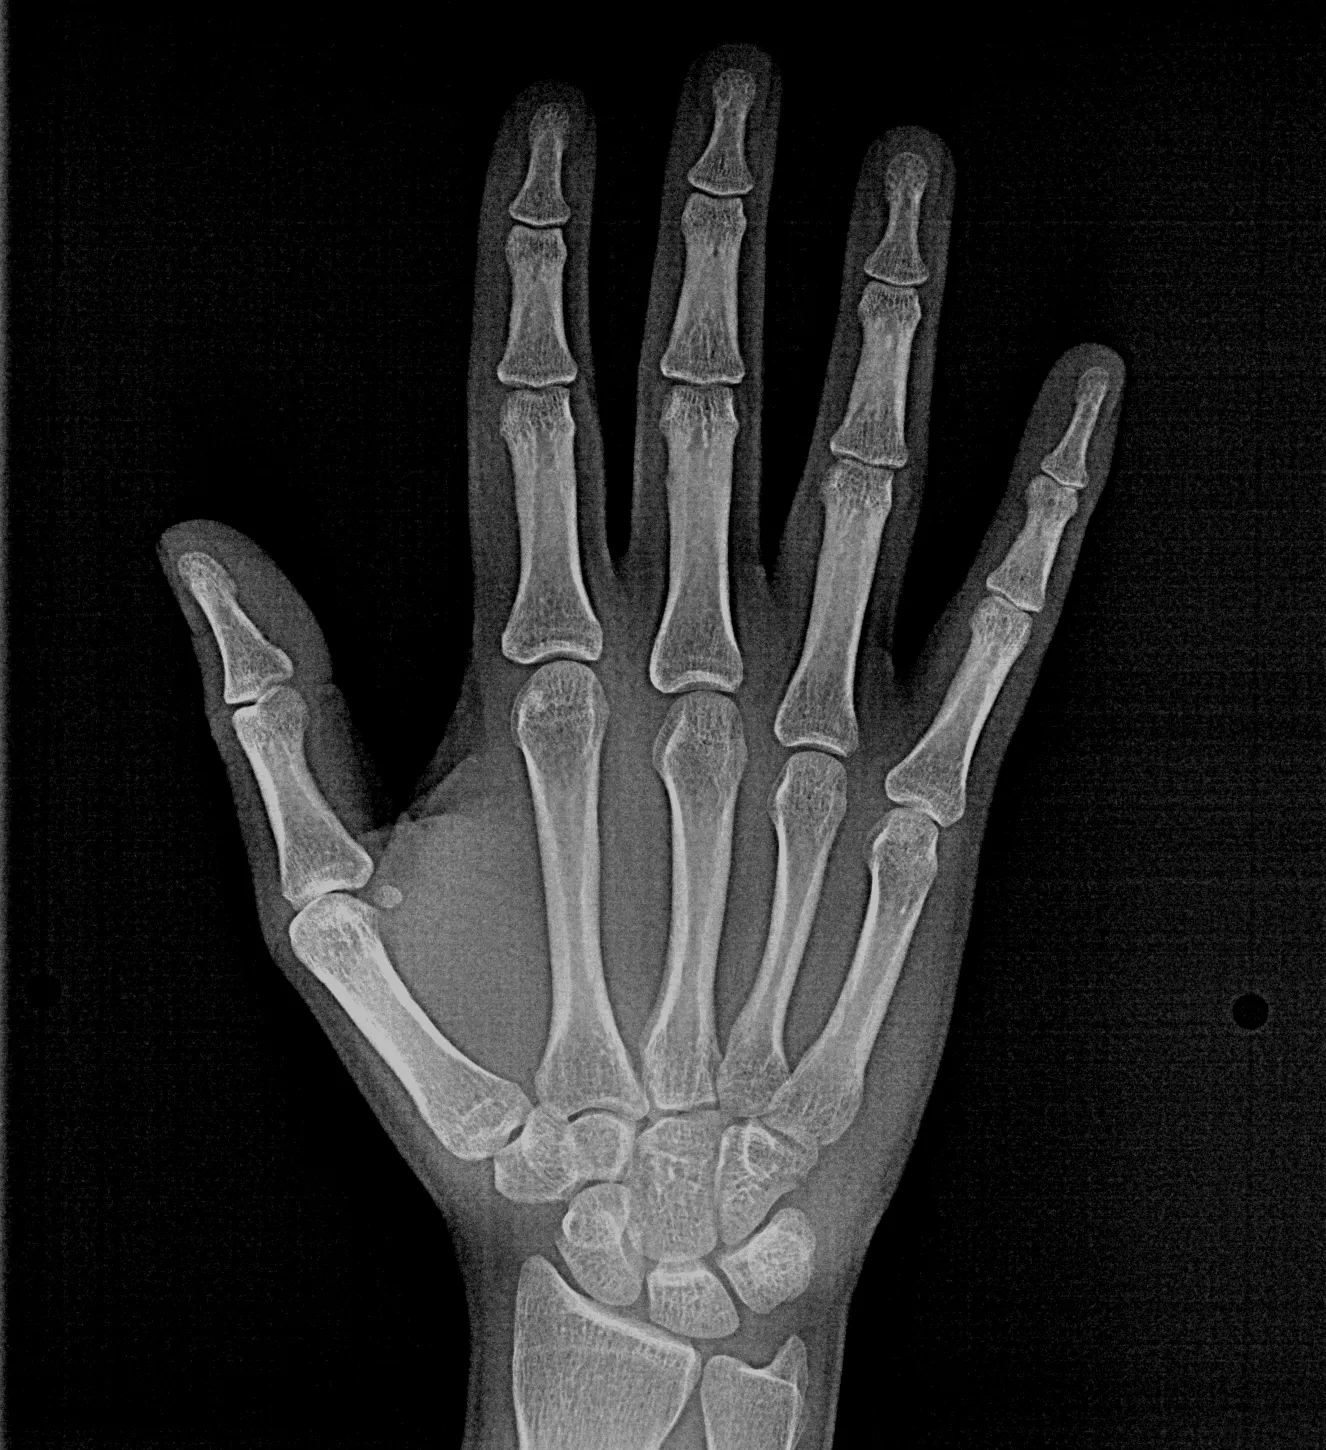

Las radiografías extraorales permiten obtener imágenes completas de los maxilares, la articulación temporomandibular (ATM) y las estructuras faciales sin colocar el sensor dentro de la boca.

Realizamos estudios como radiografía panorámica, cefalométrica, de senos paranasales y de ATM, esenciales para tratamientos de ortodoncia, cirugía y diagnóstico integral.